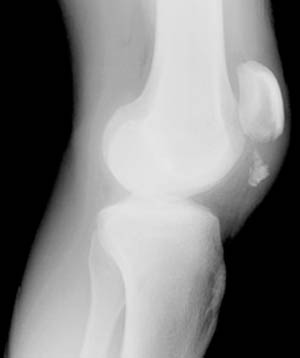

28) Name the abnormality shown in the image below.

29) Give the specific name for the fracture type shown in the image above.